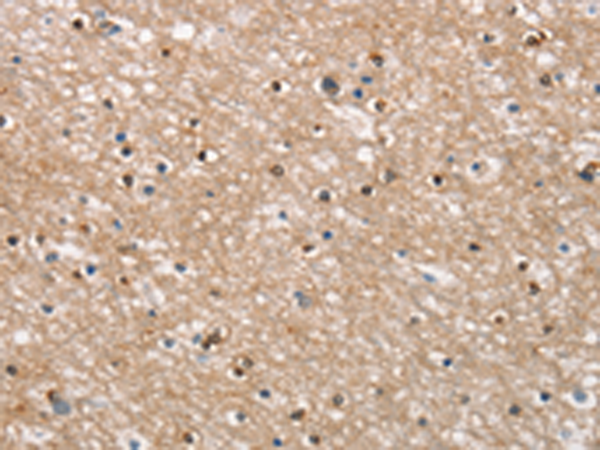

分类: 科研抗体货号: P11205别名: CL1; DCLK; CLICK1; DCDC3A; DCAMKL1应用: IHC反应种属: Human, Mouse